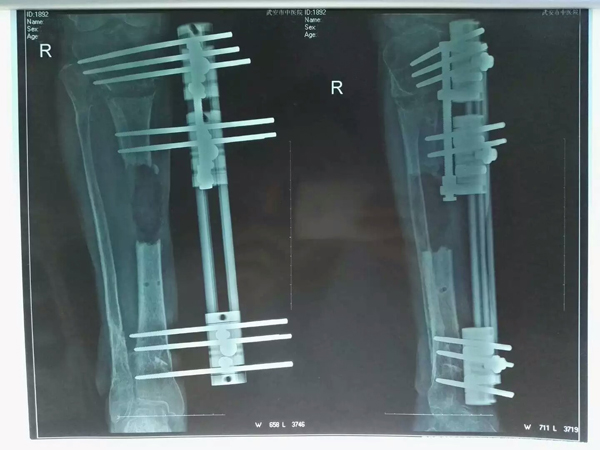

術(shù)后

骨傷二科醫(yī)生經(jīng)過(guò)充分的理論論證及實(shí)際可行性討論的基礎(chǔ)上,做了大量的術(shù)前準(zhǔn)備工作。在各種條件均允許的情況下,為患者實(shí)施了“截骨延長(zhǎng)術(shù)”。手術(shù)中首先對(duì)存在感染的骨質(zhì)進(jìn)行了大約10cm的截骨,并應(yīng)用滑動(dòng)外固定架進(jìn)行固定,再對(duì)皮膚的不愈口進(jìn)行處理,使傷口敞開(kāi)不愈,防止骨折端在延長(zhǎng)時(shí)受到阻礙,定時(shí)將滑患者出院后,中醫(yī)院骨傷二科醫(yī)生還定期向患者進(jìn)行回訪,了解患處愈合情況。該患者在家里經(jīng)過(guò)11個(gè)月的后期恢復(fù)后,骨質(zhì)斷端終于交接在一起,并有骨痂形成,遂到醫(yī)院取下外固定架,并囑咐患者早期在雙拐支撐下進(jìn)行緩慢鍛煉,逐步改為單拐下進(jìn)行康復(fù)鍛煉,經(jīng)過(guò)這樣循序漸進(jìn)的康復(fù)鍛煉,病人終于可以不在任何輔助工具下自行活動(dòng)了。